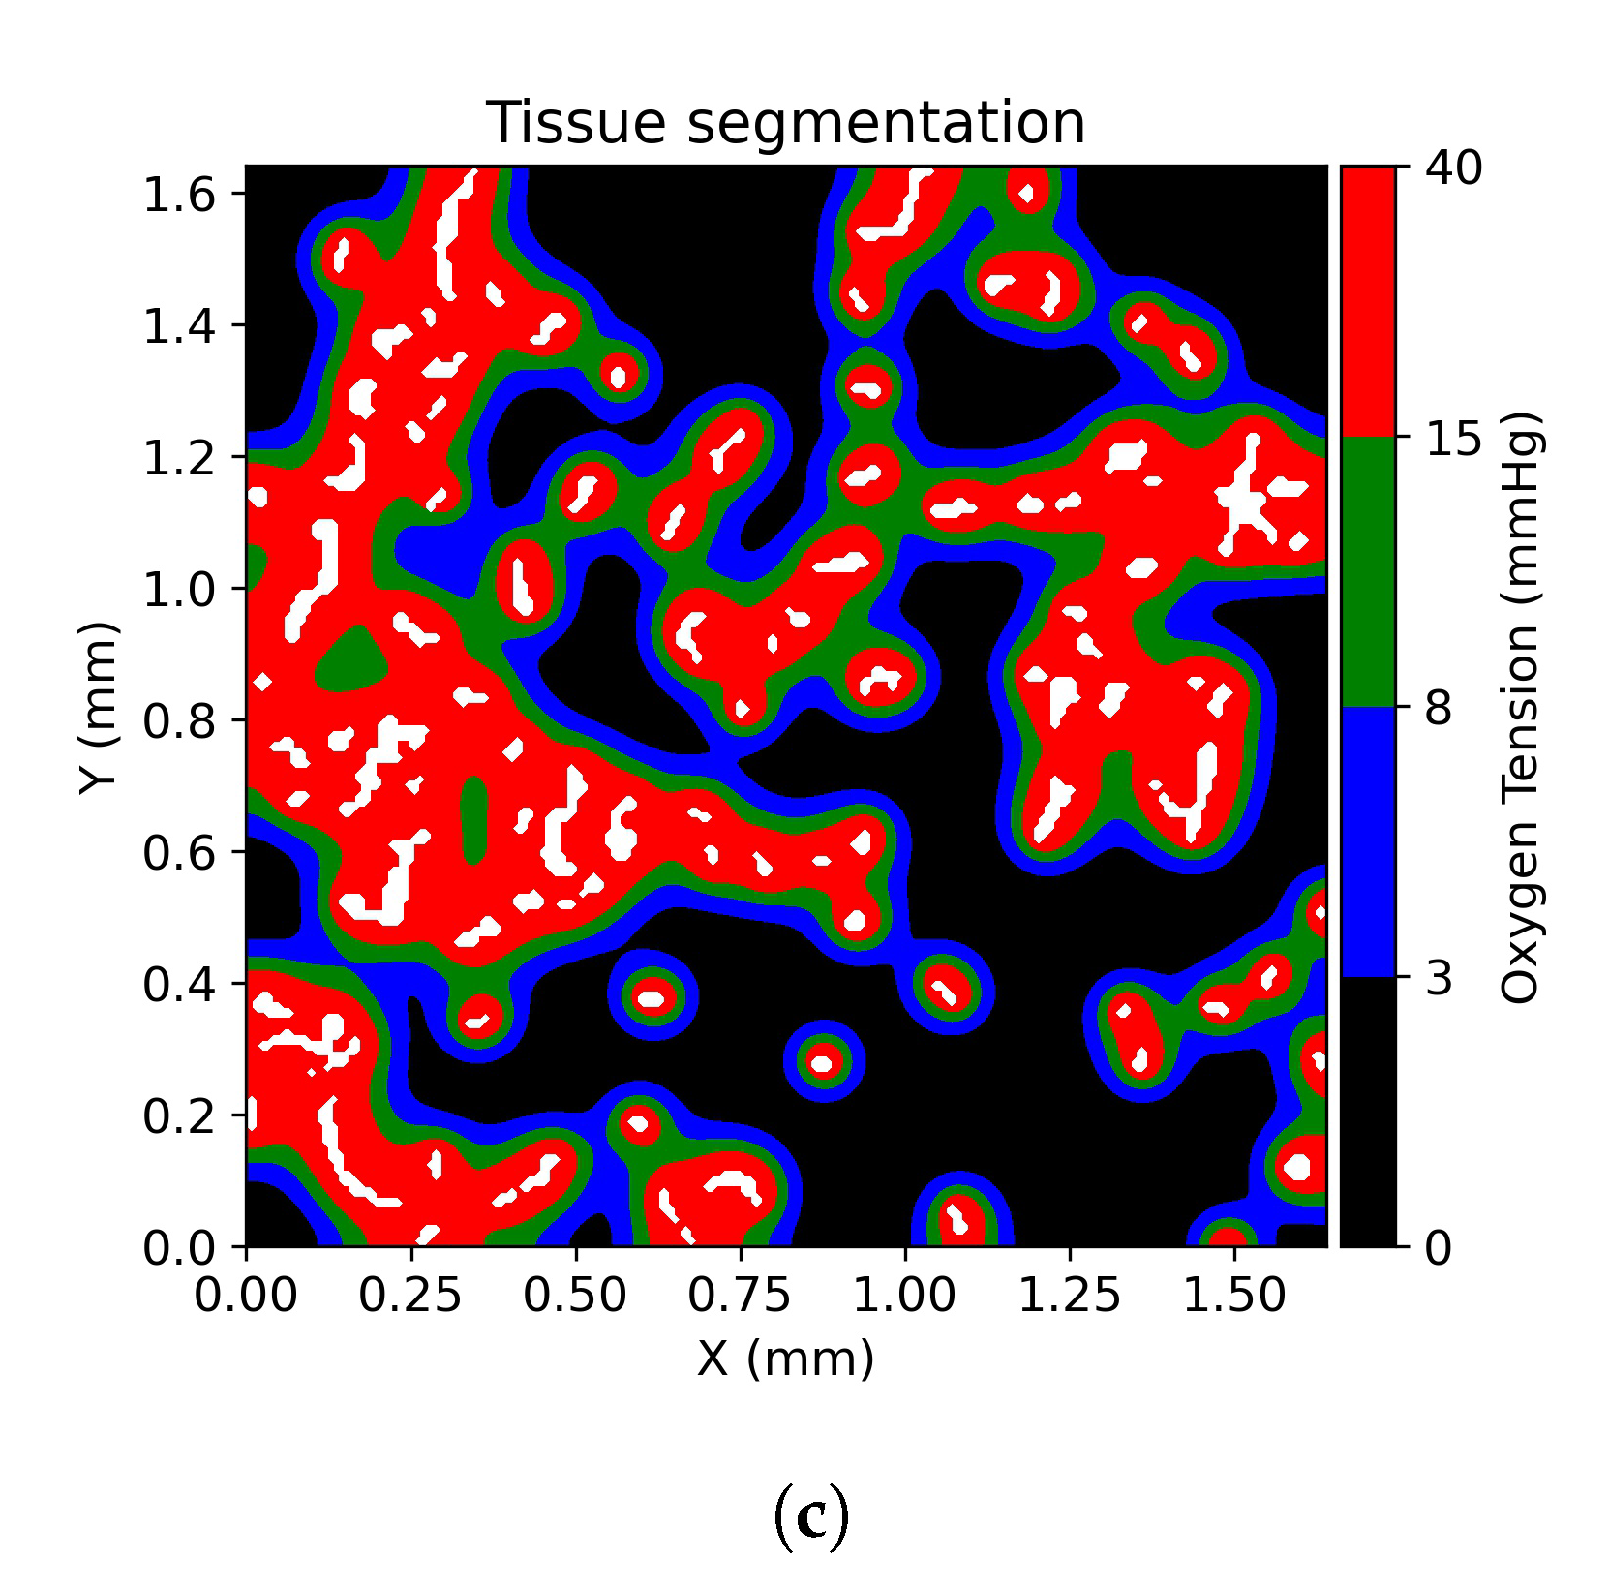

2.2. Stained Tumor Sections

2.3. Computational Domain and Vessel Map Generation